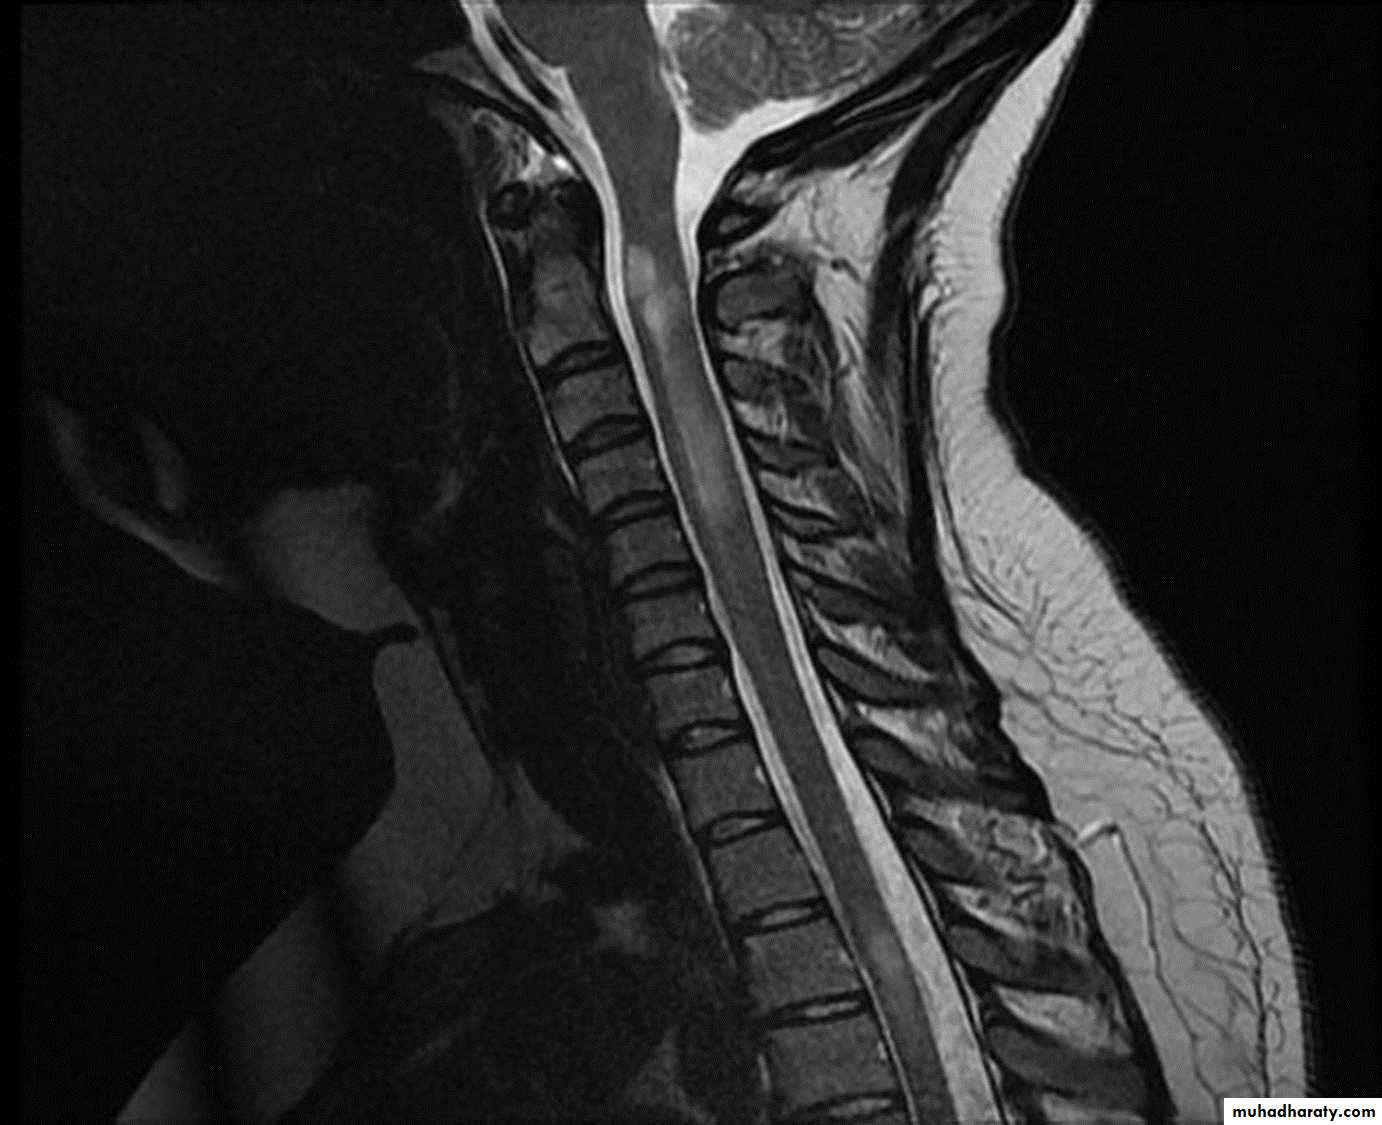

A T2-weighted MRI image of her spinal cord shows a lesion extending from T1 to T5 and affecting the central cord. The lesion shows patchy enhancement with gadolinium.